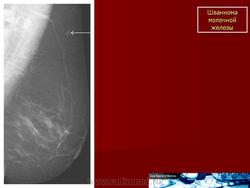

Шваннома.